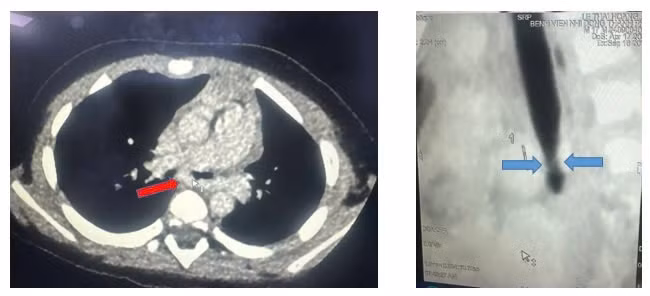

CT scan ngực mặt cắt ngang thấy động mạch phổi trái quấn hẹp khí quản gốc, mặt cắt dọc đứng thấy hẹp khí quản gốc (carina).

Kết quả ghi nhận, khí quản gốc chỗ chia đôi phế quản phải trái (carina) có động mạch phổi trái vòng qua phải ôm lấy rồi đi qua phổi trái gây chèn ép đường thở.